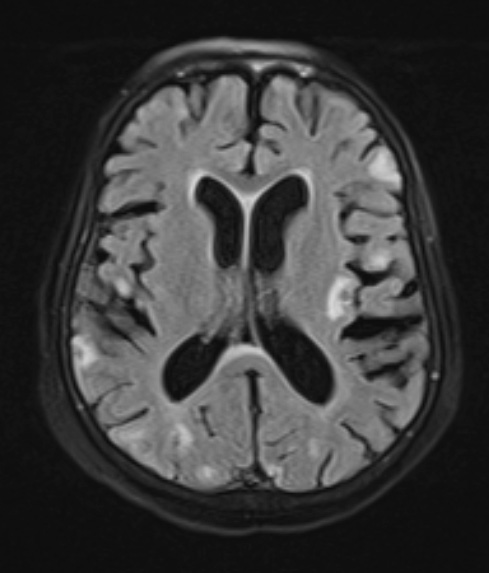

A T2-weighted FLAIR scan shows numerous cerebral lesions, many at the cortical gray/white matter junction.